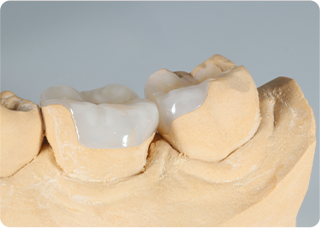

セラミックアンレー症例③

術前

ラバーダム防湿

技工物

術後

| 主訴 | 左下奥歯のむし歯の治療をしたい、良い素材での治療を希望 |

|---|---|

| 治療期間/回数 | 2週間、2回 |

| 価格(税込) | 154,000円(税込) |

| リスク・副作用 | セラミックの破損、一時的な知覚過敏が生じる場合がある |

| ポイント | むし歯を染め出すう蝕検知液を使用し、選択的にむし歯のみを除去。むし歯を除去後、すぐに詰め物でカバーをし、接着力の向上と歯を保護した。当院ではセラミック専門の歯科技工士によって精度の高いセラミックを作製。精度の高いセラミックを作製。またセラミック装着時にラバーダム防湿を行うことで、詰め物の接着効果が最大限発揮できるようにしている。 |